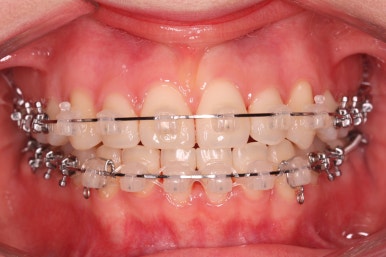

좀 더 디테일한 과정을 거치고 ㅂㄹ써 마무리가 되었습니다.

위아랫니가 매우 가지런해졌고 고민하셨던 덧니도 말끔히 개선되었습니다.

부산부정교합 키다리아저씨치과에서 이번 덧니 환자분을 치료하는데 걸린 총 기간은 14개월이였습니다.

14개월만에 치아는 가지런해졌고, 위아래 치열의 중앙도 맞아졌으며 발치를 하지 않았음에도 치열이 뻐드러지거나 돌출되지 않았습니다.

전반적으로 매우 좋아졌습니다.

또한 오히려 부각되었던 대문니의 뻐드러짐이 치료 후 개선이 되었고 웃는 모습도 굉장히 예뻐졌습니다.